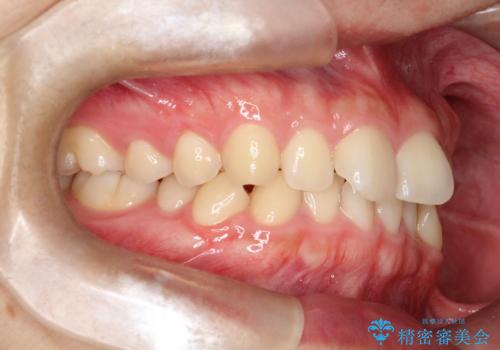

前歯のガタツキを改善する治療法として、マウスピース矯正が適していることが多いです。

マウスピース矯正は、金属製のブラケットやワイヤーを使用せずに、透明なマウスピースを装着して歯を移動させる方法です。そのため、目立たず、痛みも少ないです。